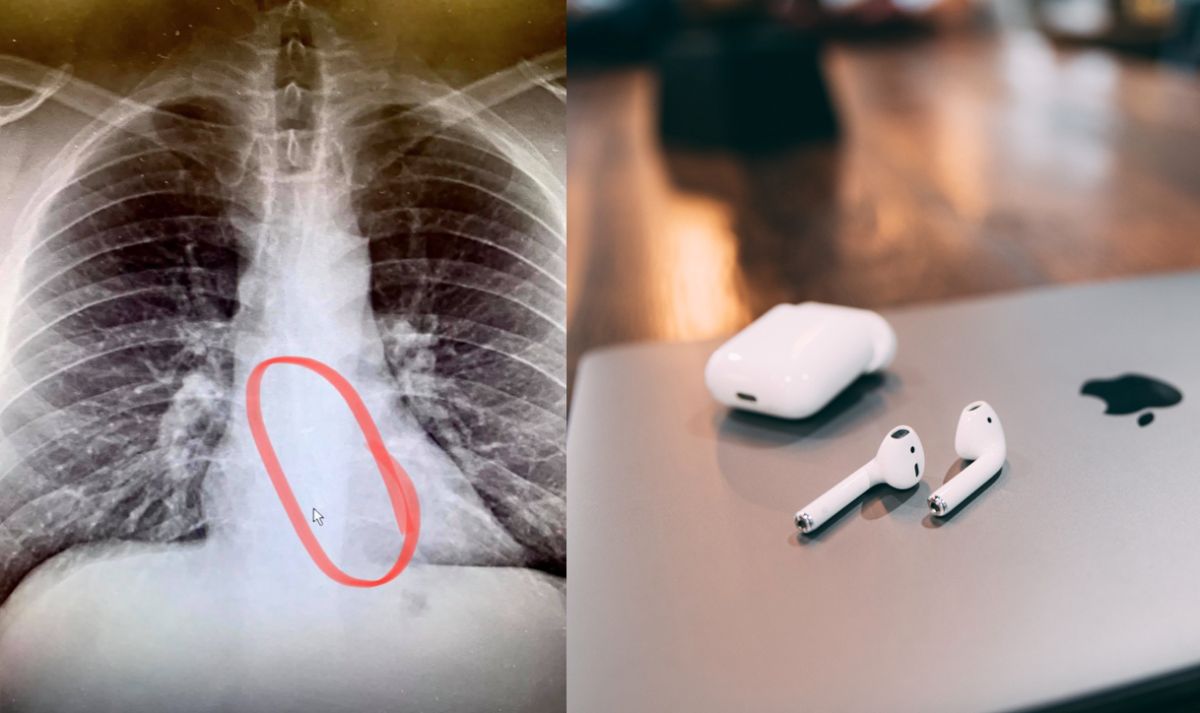

根據外媒《NBC》報導,該起事件發生在美國麻州,一名住在伍斯特市(Worcester)的男子高迪耶(Bradford Gauthier),1日晚上在住家外面鏟雪鏟了2小時,後來他感到非常疲憊,於是就戴上Airpods回房間休息,豈料2日早上一起來,就發現一邊耳機不見了。

他起床後覺得喉嚨有點不舒服,想喝杯水卻吞不太下去,當時他還以為應該只是感冒,但就在他覺得身體不適時,也突然想起昨晚自己戴著Airpods睡著了,且起床後,他也找不到另外一邊的耳機,這時在一旁的孩子還開玩笑地表示「你該不會把耳機吞下肚了吧」。

而男子得知後也超傻眼,他後來也表示,「我從沒想過戴著耳機睡著會有安全疑慮」,但他也慶幸自己還算幸運,耳機夾出後並沒有後遺症,但可惜的是,被吞下肚的耳機已經不能用了。(編輯:郭佩蓉)